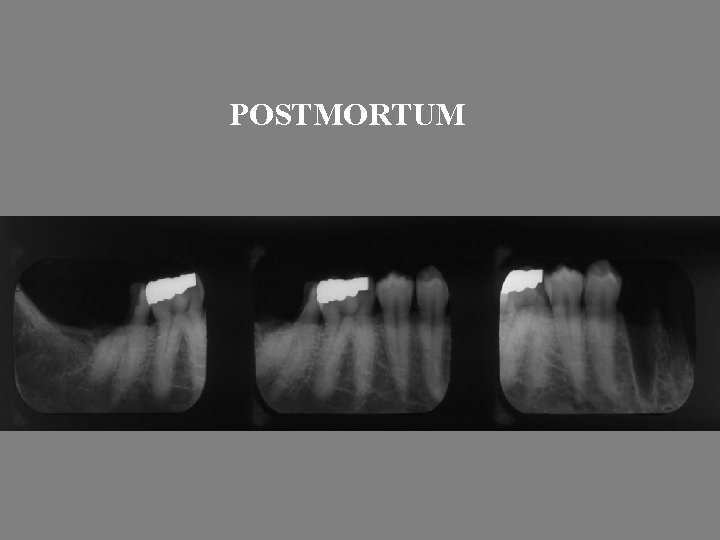

Identification of Human Remains • Post-Mortem resection of non-viewable remains • Radiography of intact or fragmented jaws • Charting of post-mortem examination • Obtaining and charting of ante-mortem records • Comparison of data

POSTMORTUM